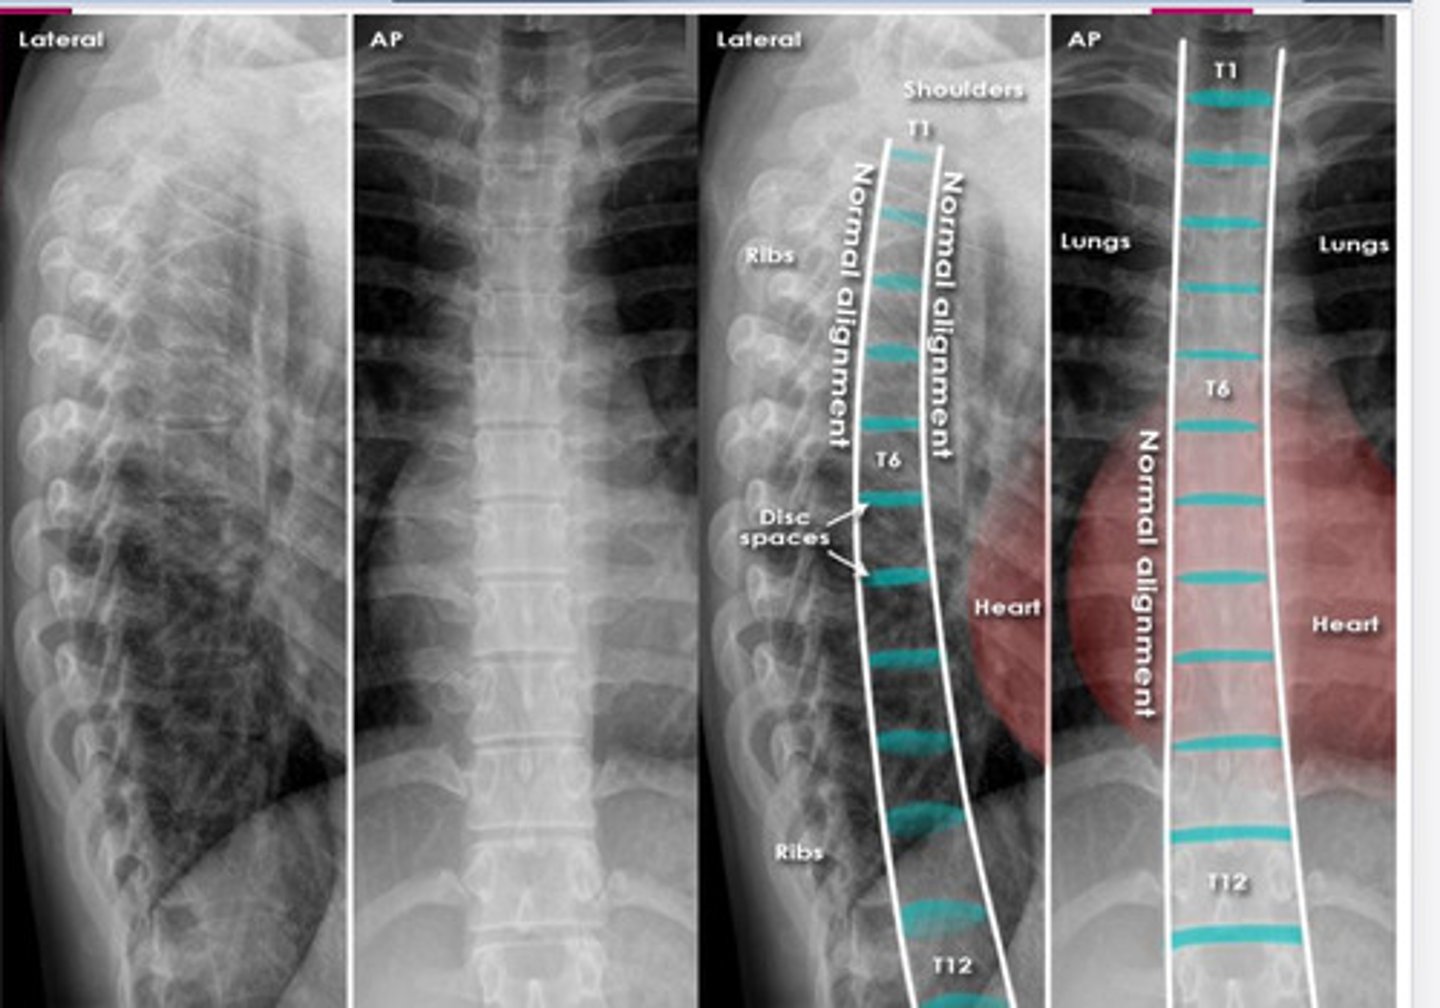

normal C/S

lateral spine xray

AP spine xray

oblique spine xray

normal thoracic spine xray

normal L/S xray